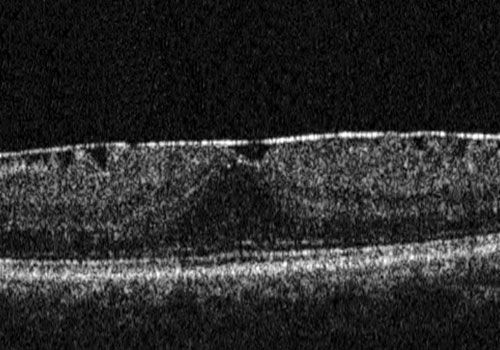

È una membrana fibrocellulare che si forma sulla superficie retinica interna per la proliferazione di cellule gliali migrate attraverso rotture della membrana limitante interna. Il risultato è rappresentato da un "raggrinzimento" della porzione centrale della retina, da cui deriva una distorsione delle immagini e un calo visivo, che può peggiorare nel tempo.

Può essere variabile in base all'entità della membrana epiretinica stessa. Nei casi più lievi (maculopatia "a cellophane") può essere asintomatica e si raccomanda solo il controllo nel tempo per valutare eventuali modificazioni.

Nei casi più gravi la membrana tende a contrarsi e a stirare la superficie retinica. Il paziente inizia a lamentarsi di una visione distorta (metamorfopsia) e di un variabile grado di diminuzione dell'acuità visiva.

L’intervento di elezione è la vitrectomia con sistemi mini invasivi (25 o 27 gauge) e prevede il peeling della membraa epiretinica e della limitante interna.